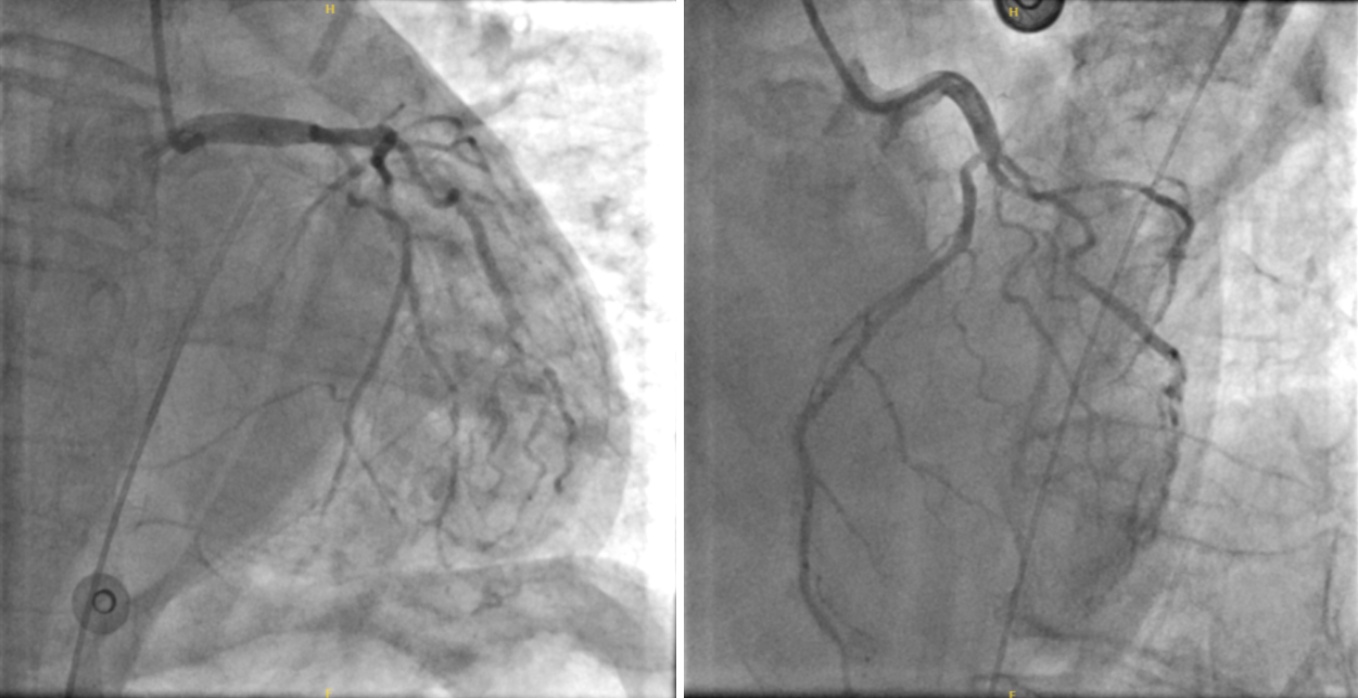

遂考虑急性心肌梗死,心源性休克,立即给予去甲肾上腺素维持血压,并行急症冠脉造影。造影结果如下(图2):

冠脉分布优势型:右优势型。

LM:头部未见明显狭窄,体部轻微斑块,尾部狭窄约30%,TIMI血流3级。

LAD:开口狭窄约40%~50%,近段轻微斑块形成,中段轻微斑块形成,远段未见明显狭窄,TIMI血流3级。

中间支:近段狭窄约80%,中远段纤细,未见明显狭窄,TIMI血流2级。

LCX:近段狭窄约50%,中段未见明显狭窄,远段未见明显狭窄,TIMI血流3级。

RCA:近段狭窄约30%~40%,中段狭窄约30%~40%,远段轻微斑块形成,TIMI血流3级。

Figure 2. The result of the emergency coronary angiography of the patient

2. 患者急诊冠脉造影结果